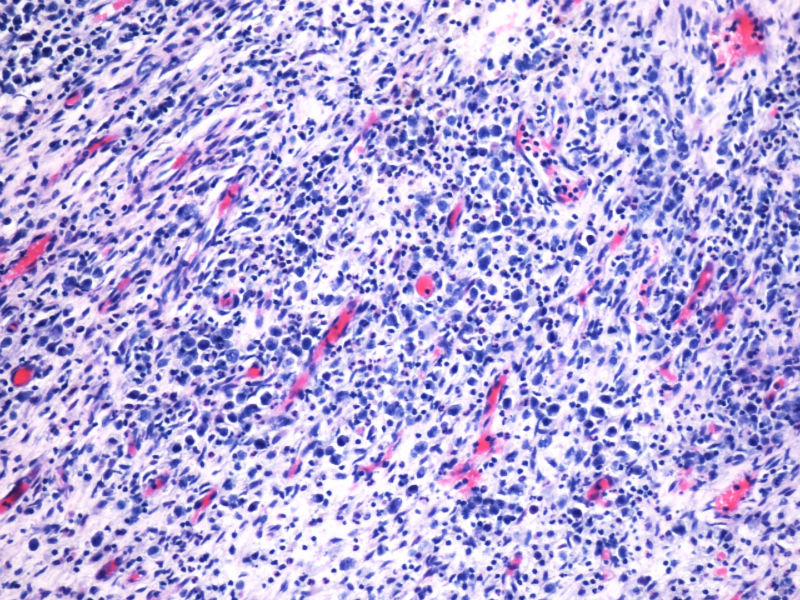

形态学hallmark 细胞显示不是很清晰,大的肿瘤细胞如果在ALCL和HL之间选择可能不容易,但HL的肿瘤细胞形态学特点的范围比较狭窄,而ALCL可能具有更广泛的形态学范围,细胞大小形态以及典型hallmark cell的多少有时很难确定。如果只看HE,觉得ALCL的可能会安全一点,当然我个人经验不足,可能理解得比较肤浅。

本例全B,全T缺失,使诊断很困难,淋巴瘤范围内一般考虑①HL;②浆细胞分化的肿瘤如浆细胞骨髓瘤或浆母细胞瘤;③ALCL. 以下为鉴别:

2.关于PAX5:应该是HL和ALCL鉴别非常好的标记。WHO: The B-cell nature of HRS cell is further demonstrable in approximately 95% of cases by their expression of the B-cell specific activator protein PAX5. 本例PAX5阴性,重点就只有放在ALCL上了。

最后,ALK+可证实以上的推断。